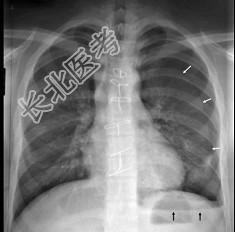

- 男,28岁, 胸闷、右肺呼吸音减弱,请结